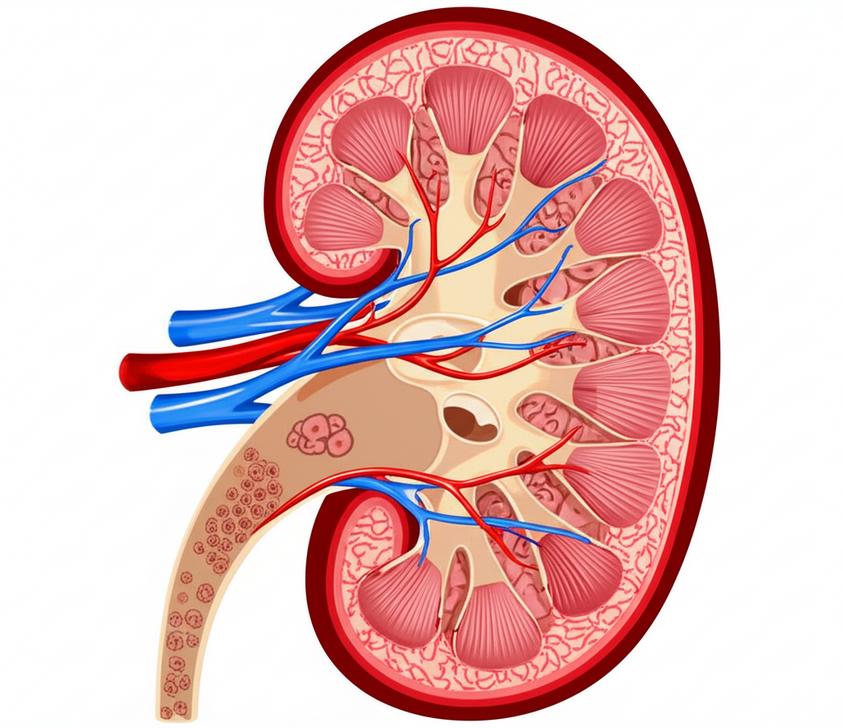

ไตเป็นอวัยวะสำคัญยิ่งต่อการดำรงชีวิต ทำหน้าที่มากกว่าแค่การขับของเสีย แต่ยังควบคุมสมดุลน้ำและแร่ธาตุในร่างกาย สร้างฮอร์โมนที่จำเป็นต่อการสร้างเม็ดเลือดแดงและการควบคุมความดันโลหิต ในมุมมองของเวชศาสตร์ชะลอวัยและฟื้นฟูสุขภาพ การทำงานของไตที่ลดลงเป็นสัญญาณสำคัญของการเสื่อมถอยของร่างกายตามวัย ซึ่งส่งผลกระทบต่อคุณภาพชีวิตโดยรวมอย่างมาก การรักษา healthy kidney function จึงมิใช่แค่การป้องกันโรค แต่เป็นการรักษาสมดุลองค์รวมของร่างกาย เพื่อให้เรามีสุขภาพที่ดีและมีอายุยืนยาวอย่างมีคุณภาพ บทความนี้จะนำเสนอแนวทางเชิงลึกในการดูแลและฟื้นฟูไต โดยเน้นการทำความเข้าใจกลไก การปรับโภชนาการ และการปรับเปลี่ยนวิถีชีวิตภายใต้หลักการแพทย์เพื่อชะลอภาวะไตเสื่อม

ไตทำหน้าที่เป็นระบบกรองที่ซับซ้อน เมื่อเวลาผ่านไป เซลล์และเนื้อเยื่อไตอาจเผชิญกับความเสียหายจากการสะสมของปัจจัยเสี่ยงต่างๆ ซึ่งนำไปสู่การทำงานที่ลดลงตามลำดับ ในมุมมองของเวชศาสตร์ชะลอวัย ภาวะไตเสื่อมมักเชื่อมโยงกับกระบวนการดังต่อไปนี้: